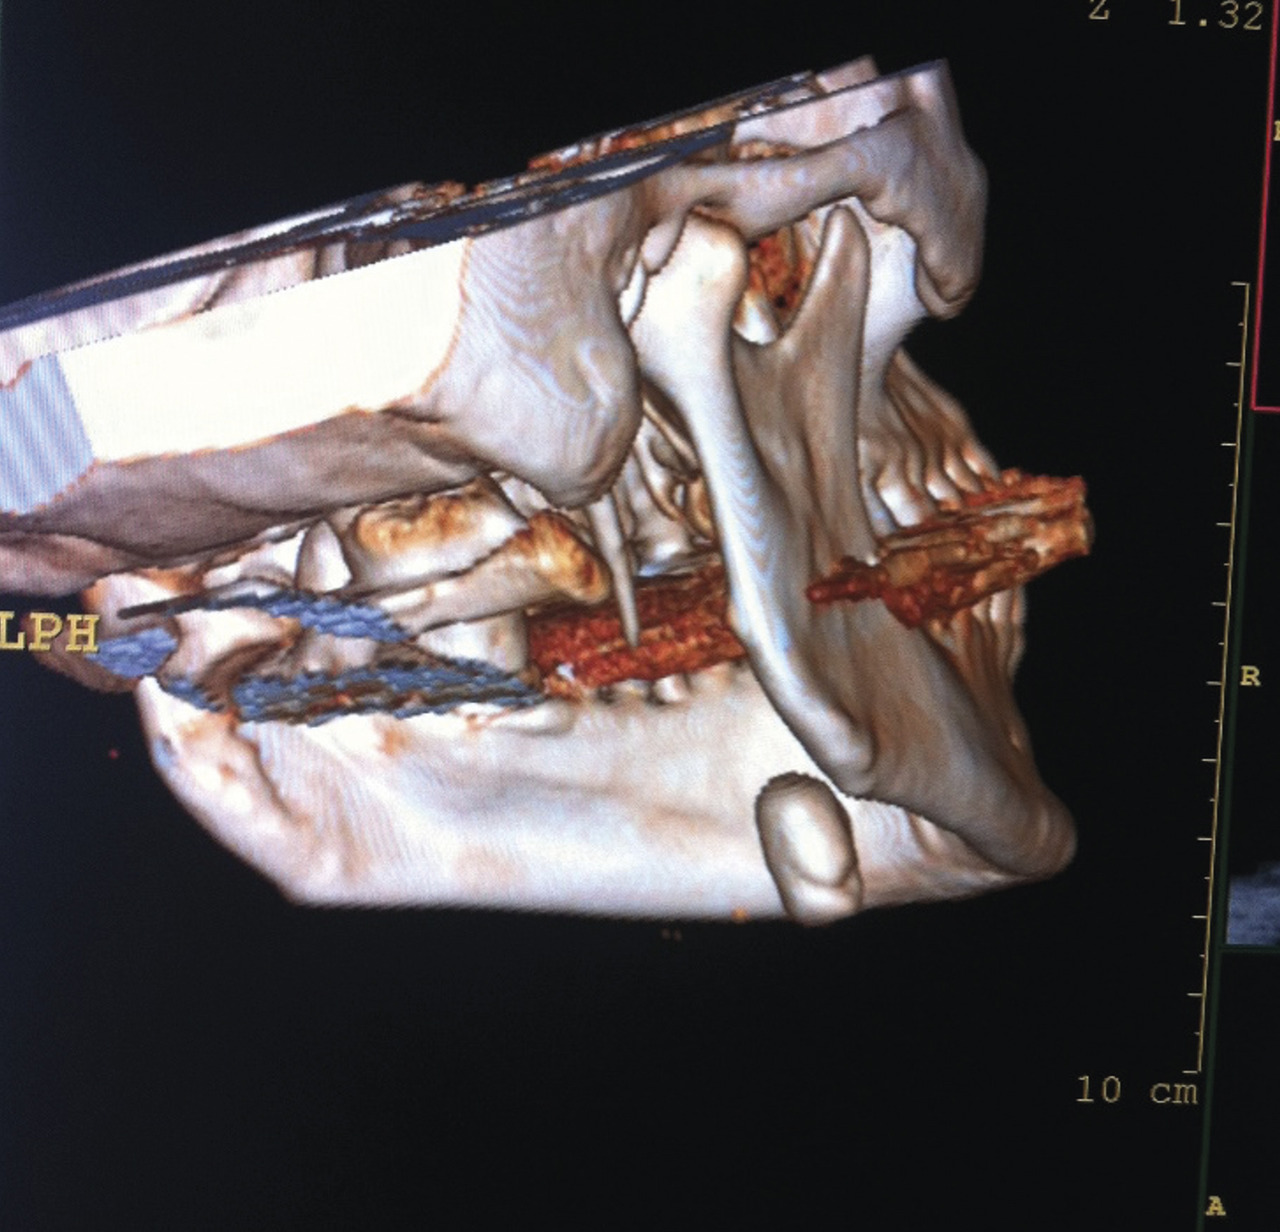

L’examen biologique est normal : absence de syndrome inflammatoire, hémogramme sans anomalie. La tomodensitométrie cervicale (fig. 2 et 3 ) montre une volumineuse formation calcifiée (20 × 15 mm). Cette masse correspond à la glande salivaire sous-mandibulaire droite totalement calcifiée, sans caractéristiques péjoratives.

L’examen biologique est normal : absence de syndrome inflammatoire, hémogramme sans anomalie. La tomodensitométrie cervicale (